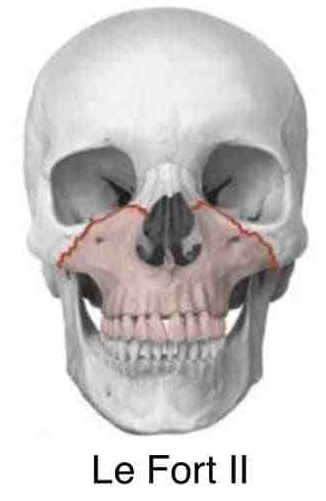

打在上颌骨上可能发生什么骨折呢?

第二型骨折(LeFort Ⅱ型骨折)的骨折线通过鼻骨、泪骨、眶底、颧骨下方,达到上颌骨后壁;

上颌骨Le Fort 骨折分型对临床诊治具有一定指导作用;除了共同临床表现之外,各型上颌骨Le Fort 骨折都具有其独特的临床表现,如:Le Fort Ⅱ型骨折会出现鼻及眶下缘的变形,常有鼻腔侧壁及上颌窦的损伤等,Le Fort Ⅲ型骨折则常形成颅面分离,使面中部凹陷、变长等;这些不同的临床表现对临床诊断有重要参考意义;各型上颌骨Le Fort 骨折在治疗上也具有一定特点,如Le Fort Ⅰ型骨折手术时多数只需采用口内前庭切口就能取得良好的疗效;而Le Fort Ⅱ、Ⅲ型骨折则多需口内前庭切口和头皮冠状切口联合应用才能获得满意的显露效果;再如Le Fort Ⅲ型骨折常伴有颅脑损伤和颅底骨折,处理时应注意颅脑损伤的诊治。